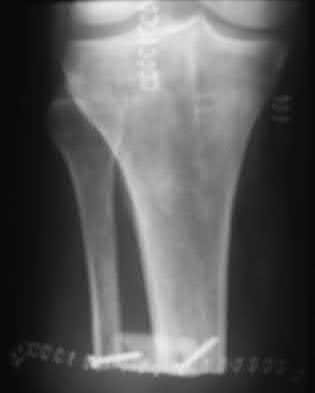

A 25-year-old female is involved in a motor vehicle collision. She presents with the isolated injury seen in Figures A through D. Her leg is swollen but her skin is intact. She has no clinical signs of compartment syndrome. Which of the following treatment options will allow for maintenance of fracture alignment and minimize the risk of soft tissue complications?

The patient presents with a closed distal third metaphyseal-diaphyseal distal tibia fracture with simple intra-articular extension. Immediate intramedullary nailing along with percutaneous fixation of the articular component provides appropriate restoration of length, rotation and alignment and minimizes the risk of wound complication.

Displaced distal third tibia fractures may be associated with simple intraarticular extension. Operative treatment of intra-articular distal tibia fractures has historically been performed with open reduction and internal fixation. Early open reduction and plate fixation of pilon fractures has been associated with high rates of infection and wound complication. In select patterns with simple articular extension, percutaneous screw fixation and medullary nailing may provide appropriate reduction with minimal soft-tissue risk.

Figures A and B demonstrate a distal third tibial shaft fracture with simple intra-articular extension. The axial and coronal CT cuts in Figures C and D further clarify the articular injury. Illustrations A and B demonstrate a comminuted distal third tibial fracture with simple intra-articular extension. Illustrations C and D are fluoroscopic images of the same injury after intramedullary nailing and percutaneous fixation of the articular component.